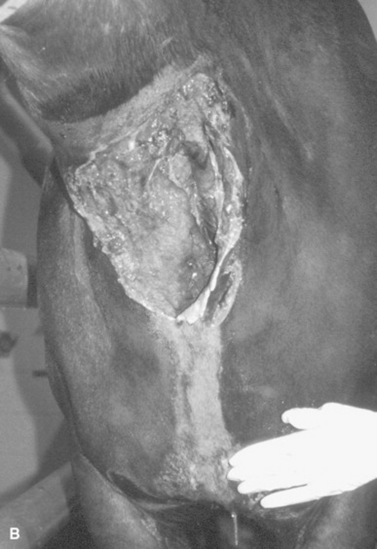

Survey radiography is generally helpful to evaluate the cervical esophagus for evidence of rupture as well as to evaluate the abdomen. Esophageal ruptures secondary to an obstruction or vigorous placement of a nasogastric tube result in a small volume of gas that tracks just dorsal to the trachea (Fig. 32-2). This can be confused with a tracheal laceration; however, with tracheal lacerations generally the gas accumulation will surround the trachea and the volume of gas within the subcutaneous tissues and the cranial mediastinum will be severe. In addition, esophageal obstructions, also called choke, can sometimes be identified on survey radiographs depending on the material that is causing the obstruction and the amount of air or contrast medium that is able to surround the structure (Fig. 32-3). Although the nature of the obstruction cannot be determined, the extent of the abnormality can sometimes be identified.

image

Fig. 32-2 Standing lateral radiograph of a 13-year-old Morgan gelding with an esophageal tear. Note the tubular region of small gas opacities caused by air trapped around the outer border of the esophagus (arrows). An esophageal perforation secondary to an ingested foreign body was confirmed with endoscopy.